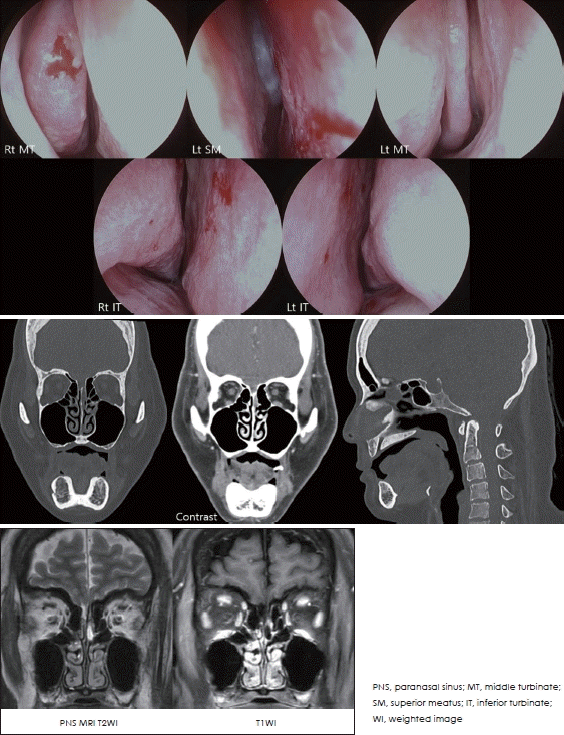

잦은 두통과 재발성 뇌수막염 과거력이 있는 51세 여자 환자가 좌측 코의 수양성 비루를 주소로 내원하였다. 비내시경, PNS CT, PNS MRI 사진은 아래와 같다. 가장 가능성이 높은 진단은?

해 설 비내시경상 좌측 상비도에 bluish한 박동성(문제에서는 생략) 종괴가 관찰되며, CT 및 MRI상 좌측 cribriform plate와 연결된 낭성(T2-weighted image [WI]에서 hyperintense, T1WI에서 hypointense) 병변이 관찰된다. 재발성 뇌수막염 병력을 고려할 때, 가장 가능성 높은 진단은 meningocele이다. Meningoencephalocele은 신경조직이 지주막하 연결을 유지한 채로 중추신경계에서 탈출한 것으로, 비강 내에서는 주로 lateral wall of sphenoid sinus (56%), cribriform plate (25%), posterior wall of frontal sinus (13%) 등에서 발생한다. 치료는 주로 endoscopic surgery이며, meningocele을 절제한 후 nasoseptal flap, abdominal fat, fascia, glue 등을 이용하여 skull base defect를 재건한다.